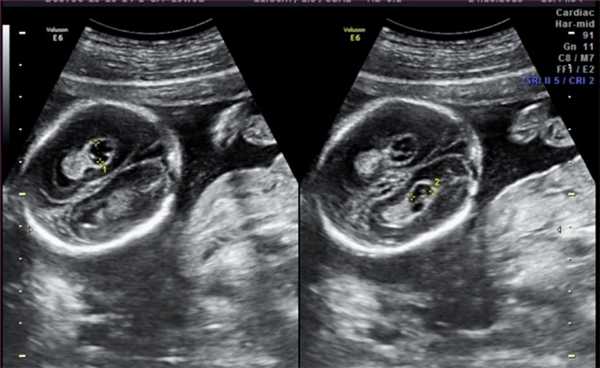

7. Расширение почечных лоханок (пиелоэктазия).

Почечные лоханки это полости, где собирается моча из почек. Из лоханок моча перемещается в мочеточники, по которым она поступает в мочевой пузырь.

Пиелоэктазия представляет собой расширение почечных лоханок. Пиелоэктазия в 3-5 раз чаще встречается у мальчиков, чем у девочек. Встречается как односторонняя, так и двухсторонняя пиелоэктазия. Легкие формы пиелоэктазии проходят чаще самостоятельно, а тяжелые иногда требуют хирургического лечения.

Причина расширения почечных лоханок у плода.

Опасна ли пиелоэктазия?

Умеренное расширение почечных лоханок, как правило, не влияет на здоровье будущего ребенка. В большинстве случаев при беременности наблюдается самопроизвольное исчезновение умеренной пиелоэктазии. Выраженная пиелоэктазия (более 10 мм) свидетельствует о значительном затруднении оттока мочи из почки. Затруднение оттока мочи из почки может нарастать, вызывая сдавление, атрофию почечной ткани и снижение функции почки.

Кроме того, нарушение оттока мочи нередко сопровождается присоединением пиелонефрита - воспаления почки, ухудшающего ее состояние. Несколько чаще расширение лоханок почек выявляется у плодов с синдромом Дауна. Однако этот маркер относится к «малым» маркерам синдрома Дауна, поэтому выявление только расширения почечных лоханок не повышает риск наличия синдрома Дауна и не является показанием к проведению других диагностических процедур. Единственное, что нужно сделать до родов - пройти контрольное УЗИ в 32 недели и еще раз оценить размеры почечных лоханок.